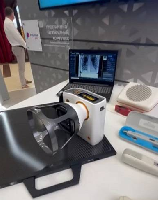

Мобильный рентгенаппарат + оцифровщик. Получение рентгеновского изображения на экране ноутбука. Вариант за 1,4 миллиона рублей под ключ.

Мобильный рентгенаппарат с печатью рентгенограмм на рентгеновской пленке. Цена 700000 рублей.